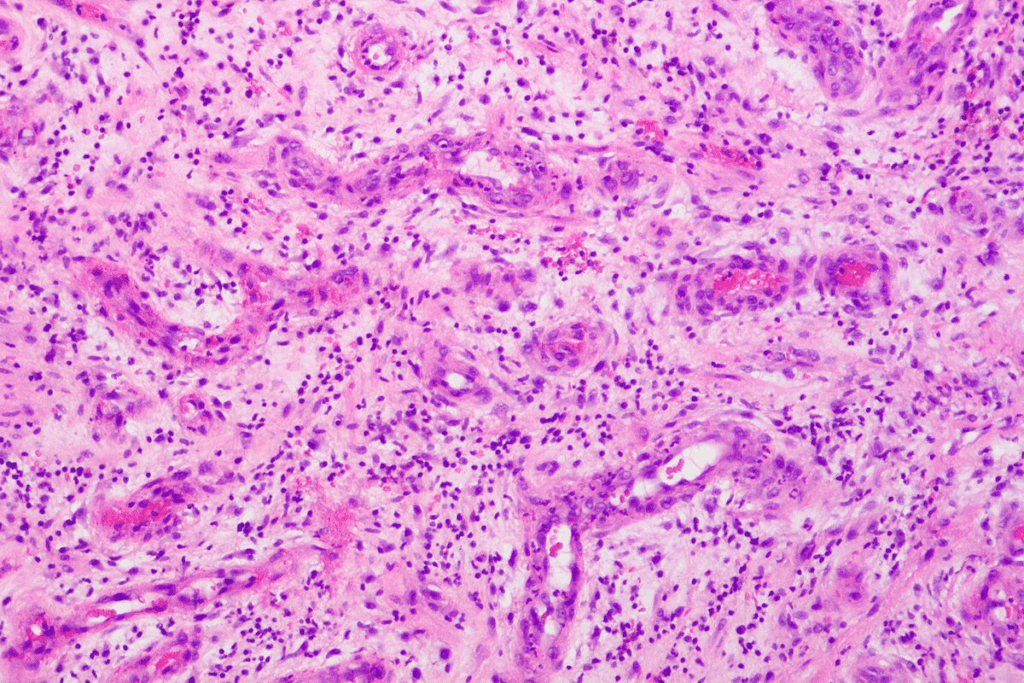

| Biopsy | To confirm neuroblastoma by examining tumor tissue |

Confirming metastatic disease is a vital step in diagnosing Stage 4 Neuroblastoma. It means finding cancer cells in distant parts of the body. Tests like the MIBG scan and bone marrow aspiration are very helpful for this.

When metastatic disease is confirmed, the diagnosis is Stage 4 Neuroblastoma. This means the disease is advanced and needs aggressive treatment.